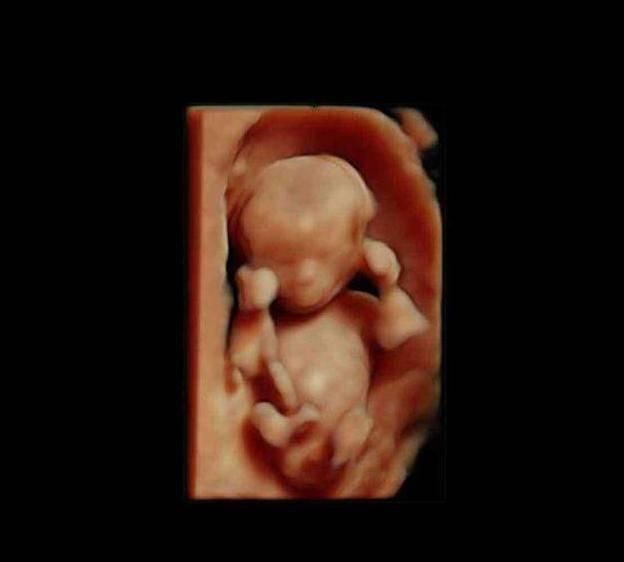

此时进入了第6周,胚胎已经具备了雏形,依稀可以卡到一个小人的形状,胚胎上下两面开始长出幼芽,将来发育成胎儿的手臂和小腿,面部器官开始形成雏形,不再是小海马的样子了。